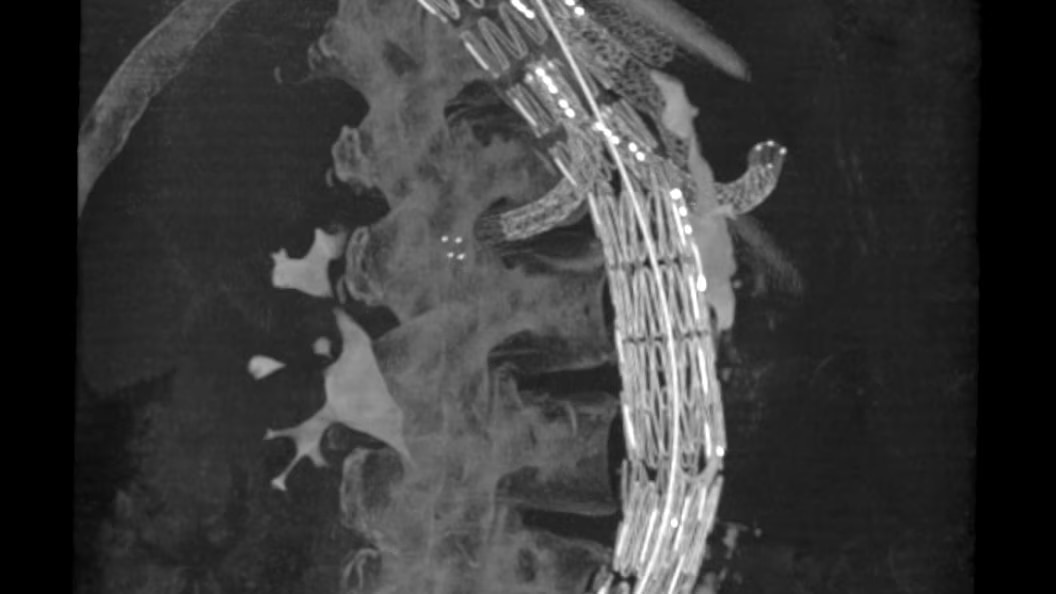

EVAR ASSIST

Perform endograft procedures in one go with intuitive tools and a simplified workflow - less radiation, more efficiency